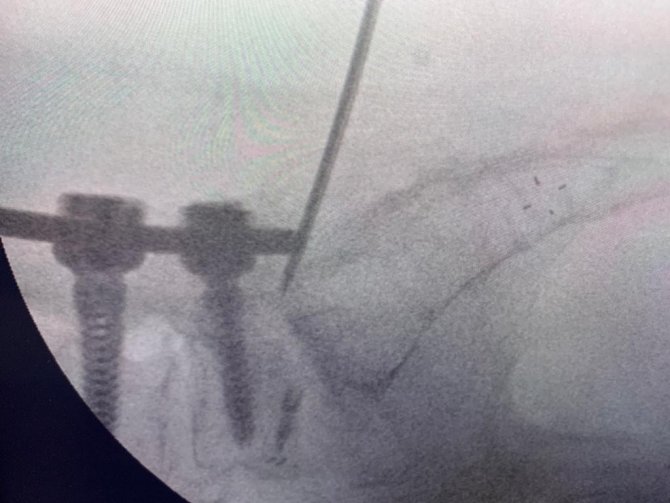

Uzun süre, vidayı çıkarmadan kemik çimentosunu koyma konusunda çalışmalar yaptığını belirten Prof. Dr. Yücesoy, "Kapalı bel fıtığı ameliyatlarında iğneyle sinirin altına girerek izlediğimiz bir yol var. "Hastaların kemiğinin içine bu yoldan girilebilir" diye düşündüm ve bunu da uygulamaya başladım. Bu yöntemde, hastaya lokal anestezi uyguluyoruz. Kıkırdağın olduğu bölümden diskin içine iğneyle girip oradan da kemiğin içine ulaşıyoruz ve çimentoyu koyuyoruz. Bu daha önce hiç uygulanmamış bir yol. Kırılmış vidalı bir kemiğe ilk kez o vidayı çıkarmadan kapalı yöntemle girip müdahale etmiş olduk" diye konuştu.